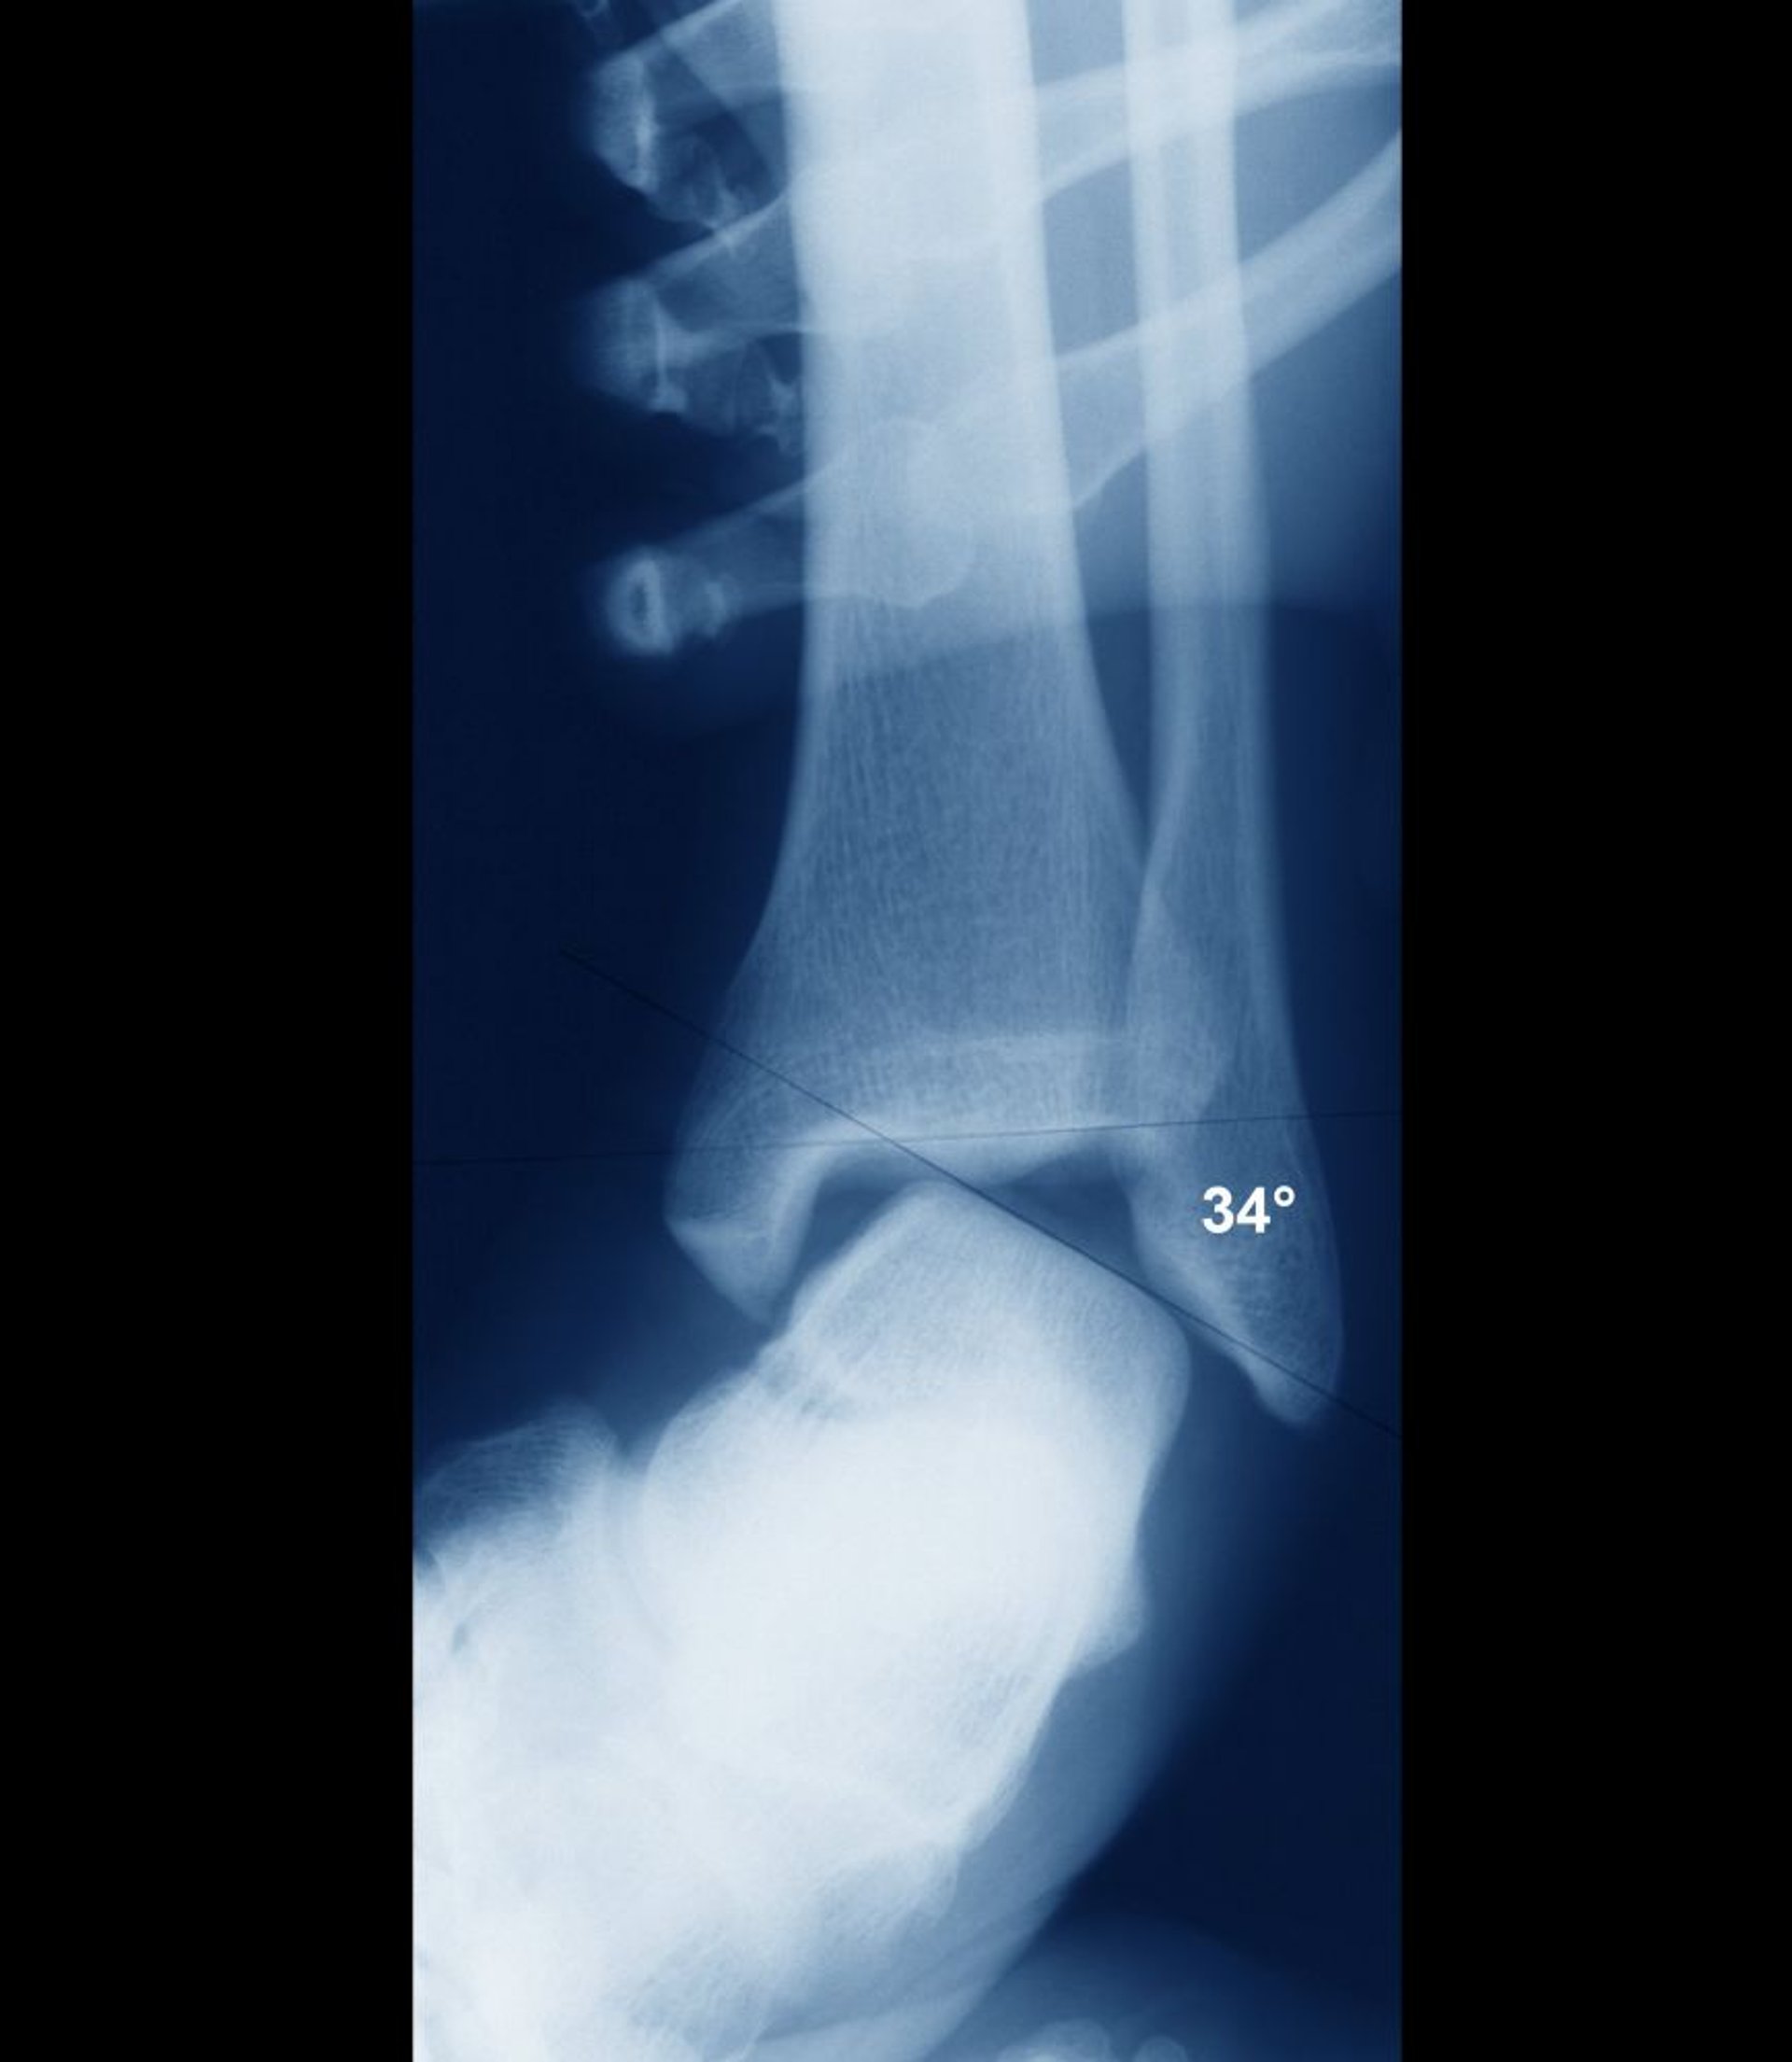

Растяжение Голеностопного Сустава С Нестабильностью

Если голеностоп стабилен, внутрисуставные поверхности таранной кости и голени должны быть параллельны. Здесь они широко расположены, что свидетельствует о серьезной нестабильности сустава. Нестабильность, как правило, оценивается клинически без необходимости рентгенограммы, как и должна была бы.